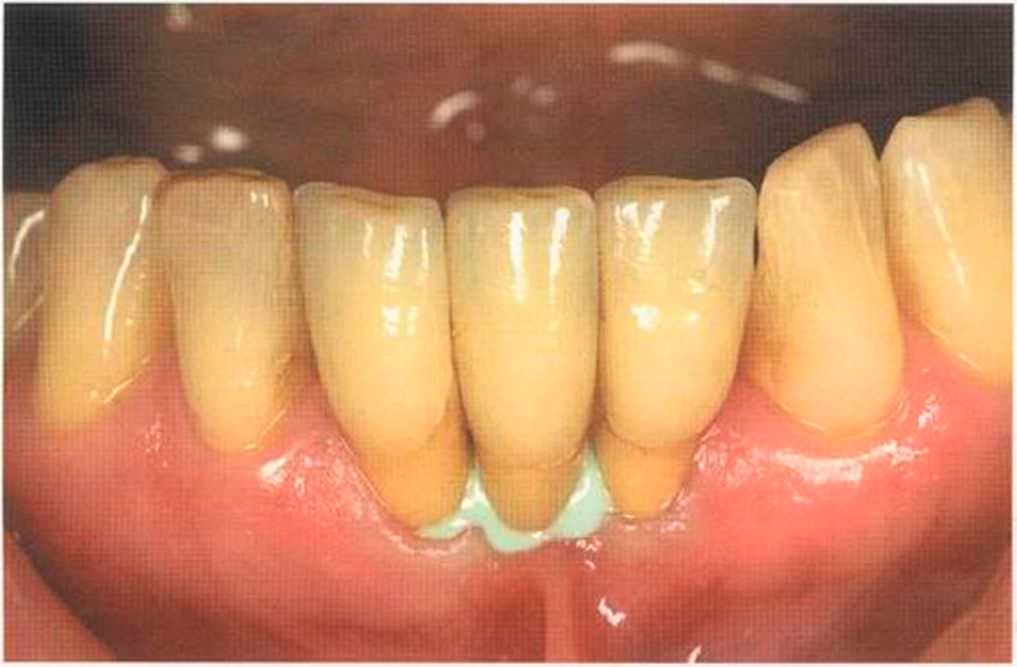

Только что зацементированные коронки. До сих пор сохранилось воспаление десневого сосочка. Уже через несколько дней он будет здоровым, бледно-розового цвета.

Зафиксированные на цемент коронки в полости рта. Видны излишки цемента, которые потом легко удалить, они отскакивают, как яичная скорлупа.